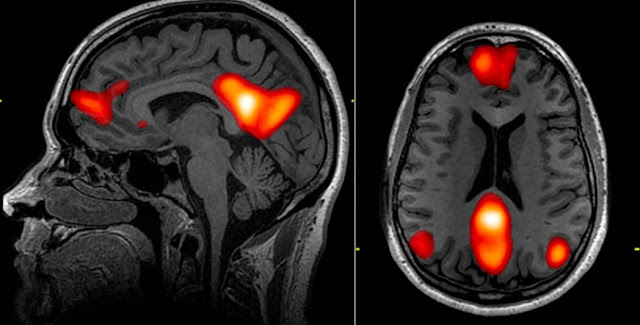

Il mercurio e alluminio sono stati a lungo dibattuti da persone come Robert Kennedy Jr . come ingredienti nei vaccini che potrebbero causare autismo; e per una buona ragione poiché sappiamo che sia l'alluminio che il mercurio sono neurotossine che danneggiano il corpo ad alti livelli. Ma ora i ricercatori hanno scoperto che l'alluminio induce la membrana a separare il cervello dal sangue che scorre verso di essa, influenzando così la sua temperatura interna, le cellule non neuronali e le cellule infiammatorie, ha riferito Daily Mail .